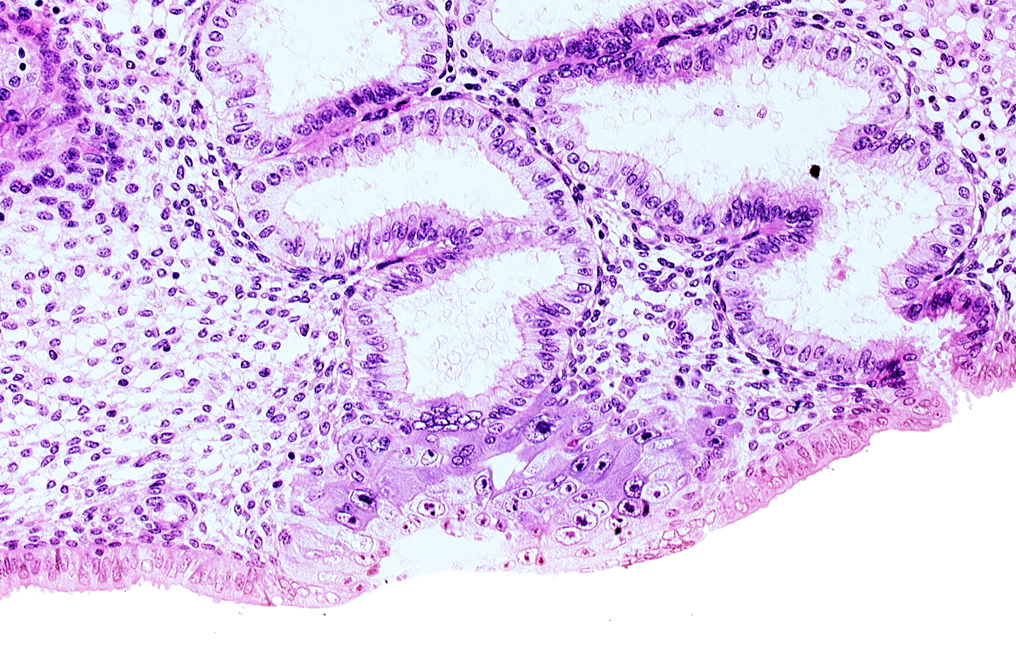

blastocystic cavity (blastocoele), cytotrophoblast, endometrial epithelium, endometrial sinusoid, junction of endometrial gland and syncytiotrophoblast, membranous trophoblast at abembryonic pole, space(s) within syncytiotrophoblast

Carnegie Embryo #8020   |   Location: 05-05-08

Keywords: blastocystic cavity (blastocoele), cytotrophoblast, endometrial epithelium, endometrial sinusoid, junction of endometrial gland and syncytiotrophoblast, membranous trophoblast at abembryonic pole, space(s) within syncytiotrophoblast